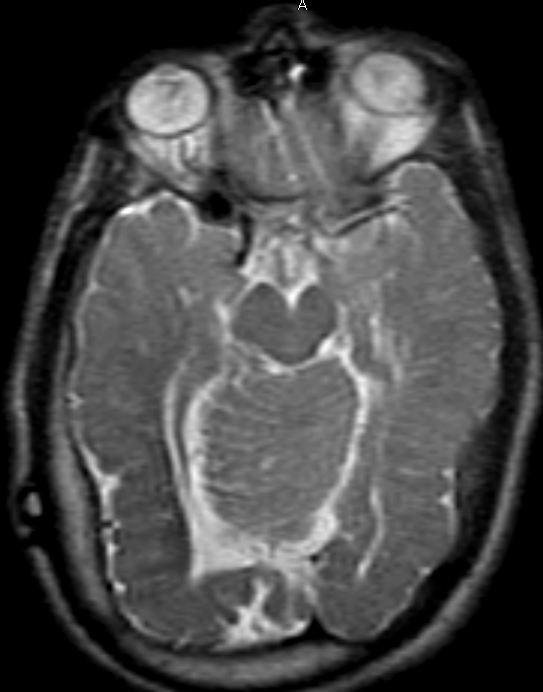

Parallel ventricles

Radial or pallisading gyri in sagittal plane

Colpocephaly

Longhorn or Viking helmit frontal horns

High riding 3rd vent

“Keyhole” temporal horns

Vascular anomalies: “wandering ACAs”

All 3 commissures are absent.

Cingulate gyrus (black arrows) “mirrors” the development of the corpus callosum.

Enlarged HC connects fornices, not cerebral hemispheres